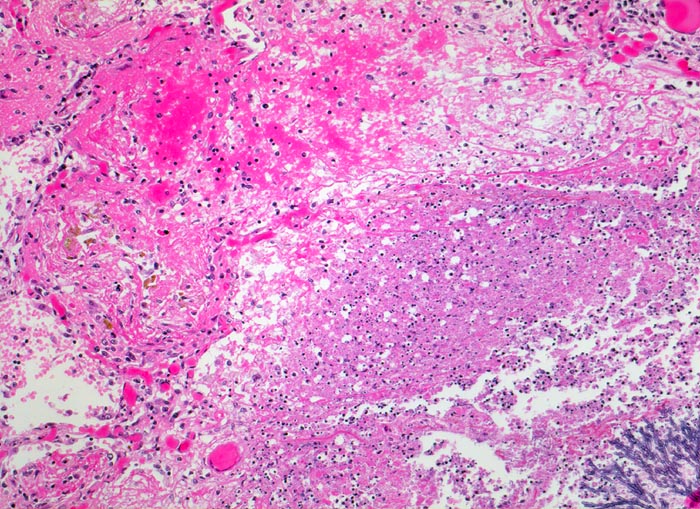

Randbereich eines Infiltratherdes. Angrenzend an die Pilzkolonie folgt ein Saum von zerfallenden neutrophilen Granulozyten und weiter aussen vitales Lungenparenchym mit hyperämischen Kapillaren und intraalveolären fädigen Fibrinexsudaten mit Einschluss von hämosiderinbeladenen Makrophagen.

Seit 14 Monaten bekannte chronische lymphatische Leukämie behandelt mit Chemotherapie. Der Patient entwickelt unter Therapie eine Pneumonie und verstirbt an einer Pilzsepsis.